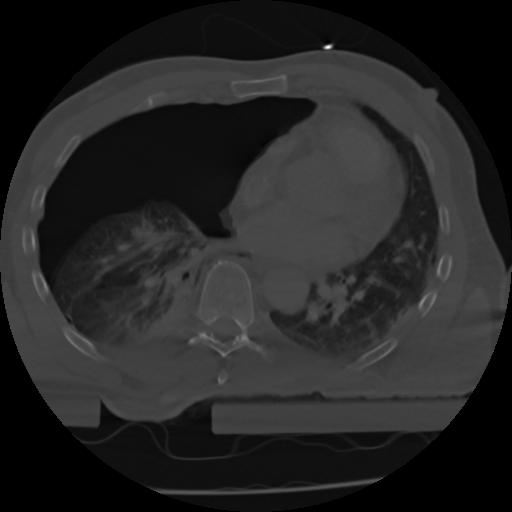

21 ANGIO,CE,Axial,3.0,ANGIO,,